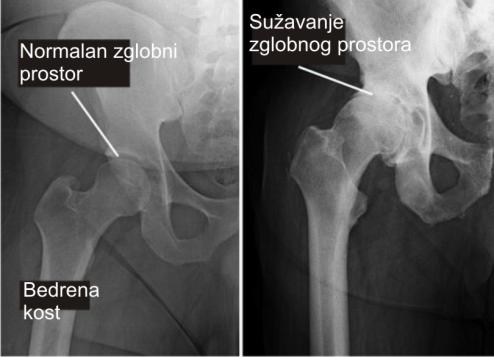

OSTEOARTRITIS KUKOVA

Slika 1

Osteoarthritis i reumatoidni artritis najčešći su uzroci boli u kuku, osobito u starijoj životnoj dobi. Artritis uzrokuje upalu zgloba kuka i razaranje hrskavice koja ublažava trenje i udarce koštanih struktura u zglobu

Kao što možemo vidjeti iz gore navedenog teksta uzrok boli u području kuka je na prvom mjestu upravo osteoartritis. Osteartritis ( artroza ) kuka ( slika 8 ) spada u kategoriju degenerativnih bolesti zgloba kod koje dolazi do trošenja hrskavica na zglobnim površinama što u konačnosti dovodi do trenja kost o kost pri pokretima zgloba i posljedično prisutne boli

Slika 8